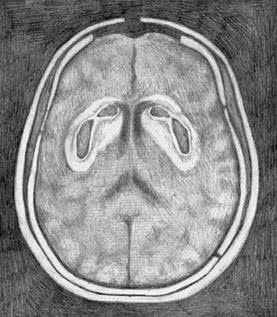

Если, прочитав это, вы почувствовали отчаяние и ужас от мысли, что придется жить без муки и сахара, я хочу заметить, что вот это – голос ваших подавленных дофаминовых рецепторов. Поразительно, насколько сильным может быть это чувство. Кажется, что раз мы отказываемся от этой еды, то в жизни больше не осталось ничего стоящего. Я знаю, как это невыносимо. И вы справитесь, уверяю вас. Дофаминовые рецепторы способны восстанавливаться. И вы снова будете в порядке. Больше чем в порядке – более уверены в себе, свободны от вреда, который эти вещества причиняли вашему мозгу. На рисунке – результаты компьютерной томографии мозга трех разных людей на участке, где в прилежащем ядре располагаются дофаминовые рецепторы. Слева – нормальный мозг, со здоровыми рецепторами, что видно по интенсивности темного участка: чем глубже тень, тем больше неврологическая активность. В центре – снимок мозга человека с кокаиновой зависимостью. Заметьте, что дофаминовый ответ весьма ослаблен. Но посмотрите, справа – мозг человека, страдающего от ожирения. Видите, насколько бледная тень? Дофаминовый ответ еще ниже, чем у человека с кокаиновой зависимостью. Один из ведущих научных принципов заключается в следующем: корреляция не означает причинность. Другими словами, возможно, что не переедание становится причиной истощения дофаминовых рецепторов, а наоборот. Возможно, что мозг человека с ожирением приказывает телу есть так много, потому что его дофаминовые рецепторы изначально были несовершенны. ![]() Нормальный мозг со здоровыми дофаминовыми рецепторами ![]() Мозг человека с кокаиновой зависимостью ![]() Мозг человека, страдающего от ожирения Ученые брали в расчет эту теорию вплоть до мая 2010 года, когда Исследовательский институт Scripps опубликовал статью в журнале «Природа неврологии» (Nature Neuroscience) {46}. Доктор Пол Джонсон и доктор Пол Кенни взяли крыс с нормальным здоровым мозгом и разделили их на две группы. Контрольную группу кормили обычным крысиным кормом. Вторая группа питалась «диетой в стиле кафетерия», включающей в себя бекон, сосиски, чизкейки, бисквиты, глазурь и шоколад, – но только один час в сутки. Третьей группе эта еда была доступна в течение 18–23 часов в день, то есть все, что они могли есть, – пища из «крысиного буфета». Неудивительно, что третью группу постигло ожирение. Но, что более важно, в начале исследования у всех крыс был абсолютно здоровый мозг, в котором впоследствии произошло угнетение дофаминовых рецепторов. Диета в самом деле стала причиной изменений. Наука доказала то, что знает каждый, прошедший через программу «12 шагов»: пищевая зависимость в действительности существует. Она столь же реальна, как кокаиновая. Как героиновая. И с точки зрения физиологии нет никакой разницы. Поначалу исследователи поставили вопрос так: «Итак, еда – это такая же губительная субстанция, как кокаин или героин?» Но сегодня большинство ученых полагают, что речь идет о куда более пагубной зависимости. Пристрастие к сахару и муке В 2007 году в Университете Бордо команда под руководством доктора Сержа Ахмеда вводила крысам кокаин внутривенно до тех пор, пока у животных не выработалась зависимость. Затем грызунам предложили то, чего прежде никогда не давали: сладкую воду. Крыс принудили выбирать между инъекцией кокаина, на котором они уже «сидели», и подслащенной водой. Не имело значения, что использовалось в виде подсластителя, – сахар или его суррогат, – крысы предпочли сладкую воду {47}. Основываясь на этом исследовании, доктор Марк Хайман заявил, что, по его подсчетам, сахар вызывает привыкание в восемь раз сильнее, чем кокаин {48}. В эксперименте, проведенном Исследовательским институтом Scripps, грызуны добровольно перебегали участки пола под напряжением и даже оставались на них, чтобы продолжать есть пищу с высоким содержанием сахара. Степень зависимости можно измерить по силе электротока, который подопытные были готовы выдержать, только бы получить искомое вещество {49}. И степень зависимости у этих крыс достигала порогов кокаиновой или героиновой зависимости. И еще одно наблюдение: когда исследователи переводили крыс с «супераппетитной пищи» на обычный корм, те начинали голодать. Они отказывались есть что-либо, кроме переработанной высококалорийной пищи. Крысы больше не могли потреблять то, что исследователи окрестили «альтернативой салатному меню» {50}. Так откуда нам известно, какая именно пища вызывает зависимость? Некоторые популярные исследования (и исследователи) полагают, что в этом списке сахар, жир и соль {51}. Я не согласна с такой позицией. Во-первых, насколько мне известно, не существует никаких доказательств тому, что соль вызывает привыкание. По правде говоря, с солью еда становится более аппетитной, и мы потребляем больше калорий. В одном эксперименте участники съели на 11 % больше пищи, если она была должным образом посолена {52}. Но аппетитный – это не то же самое, что вызывающий привыкание. |